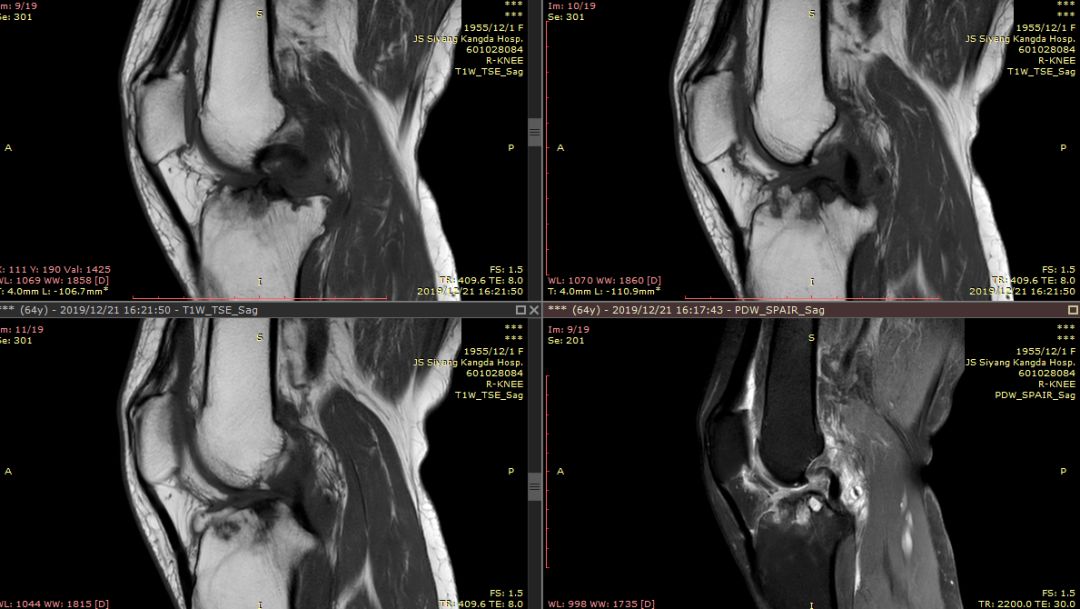

女44岁,外伤

前交叉韧带“消失”

外侧半月板后角“消失”

Segond骨折,因下肢过度内翻、内翻暴力所致胫骨平台外侧缘的撕脱性骨折。撕脱的骨折块较小,小骨片多位于腓骨头上方,且较少波及关节面而易被忽视。往往合并前交叉韧带损伤、半月板损伤及外侧副韧带损伤。

有文献报道,Segond 骨折合并有前交叉韧带(ACL)损伤的发生概率约为75%~100%,若没有得到及时处理,关节将会出现反复扭伤的现象,容易引发膝关节继发性损害,最终将导致关节过早的出现退变和骨关节病的发生。当怀疑Segond骨折,应该做MRI检查,评价膝关节组织损伤情况。